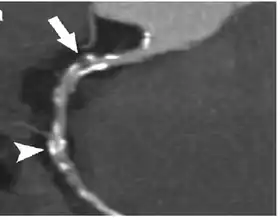

Coronary Computed Tomography Angiography (CCTA)

Computed tomography angiography (CTA), an imaging methodology using a ring-shaped machine with an X-ray source spinning around the circular path so as to bathe the inner circle with a uniform and known X-ray density. Cardiology uses are growing with the incredible developments in CT technology. Currently, multidetector CT, specially the 64 detector-CT are allowing to make cardiac studies in just a few seconds (less than 10 seconds, depending on the equipment and protocol used). These images are reconstructed using algorithms and software.

Gated Cardiac CT (CCT)

Cardiac CT (CCT) is a modified form of the traditional chest CT due to the difficulty of imaging the complex, moving heart.[16] This is achieved through the use of thin slices and high-resolution scanning, as well as the addition of electrocardiogram (ECG) gating or triggering to capture a motion-free image. Standard CT scans are acquired in either Axial or Helical modes, while CCT adds the ECG gating dimension to these modes to capture images of the heart.[16] These modifications are necessary to obtain the required data from the planar slice images, which are reconstructed from back-projected transmitted data obtained by radial excursion of the X-ray tube and detector.[16]

Coronary CT calcium scan

A coronary CT calcium scan is a computed tomography (CT) scan of the heart for the assessment of severity of coronary artery disease. Specifically, it looks for calcium deposits in the coronary arteries that can narrow arteries and increase the risk of heart attack.[17] This severity can be presented as Agatston score or Coronary Artery Calcium (CAC) score. The CAC score is an independent marker of risk for cardiac events, cardiac mortality, and all-cause mortality.[18] In addition, it provides additional prognostic information to other cardiovascular risk markers.[18] A typical coronary CT calcium scan is done without the use of radiocontrast dye, but it can possibly be done from contrast-enhanced images as well, such as in coronary CT angiography.[19]